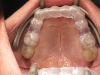

A 69-year-old male patient presented with a complaint of significant dental pain when chewing. His medical history was not relevant. Clinical examination and radiographs showed a defective restoration on vital tooth No. 3. Removal of the restoration revealed a mesiodistal crack line (Figure 3) as a result of a wedging effect provoked by the defective restoration (a fractured mesial-occlusal-distal [MOD] composite resin restoration) and amplified by a nocturnal parafunctional activity (clenching without joint derangement).

Fig 3. Tooth No. 3 had a mesiodistal crack line.

Figure 3